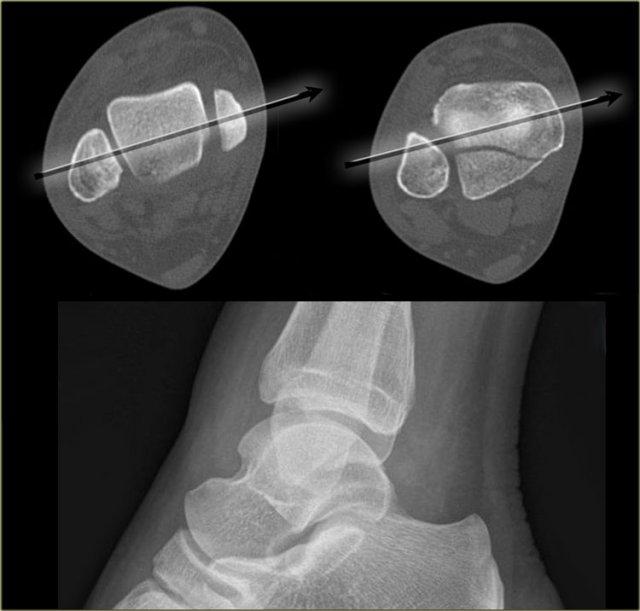

CT cho thấy một gãy xương tertius lớn.

Trên phim chụp nghiêng và cả trên phim chụp thẳng AP và phim chụp Mortise, sẽ được trình bày trong phần về gãy xương tertius, gãy xương này không thể nhìn thấy được.

Giải thích là trên phim chụp X-quang nghiêng, xương mác chiếu vào giữa xương chày.

Chùm tia X không song song với đường gãy.

Vì đường gãy của gãy xương tertius luôn có hướng này, chúng ta phải nhấn mạnh tầm quan trọng của phim chụp nghiêng thực sự.

Trên hình chụp nghiêng được định vị tốt, gãy xương tertius hiện rõ ràng (mũi tên đỏ).

Đây là gãy xương duy nhất được phát hiện trên phim X-quang cổ chân, và bệnh nhân này được xác định có gãy xương Weber-C không ổn định và phải phẫu thuật.

Chùm tia X phải được căn giữa vào các mắt cá chân.

Lưu ý sự xoay ngoài của bàn chân để có được hình ảnh nghiêng đúng chuẩn.